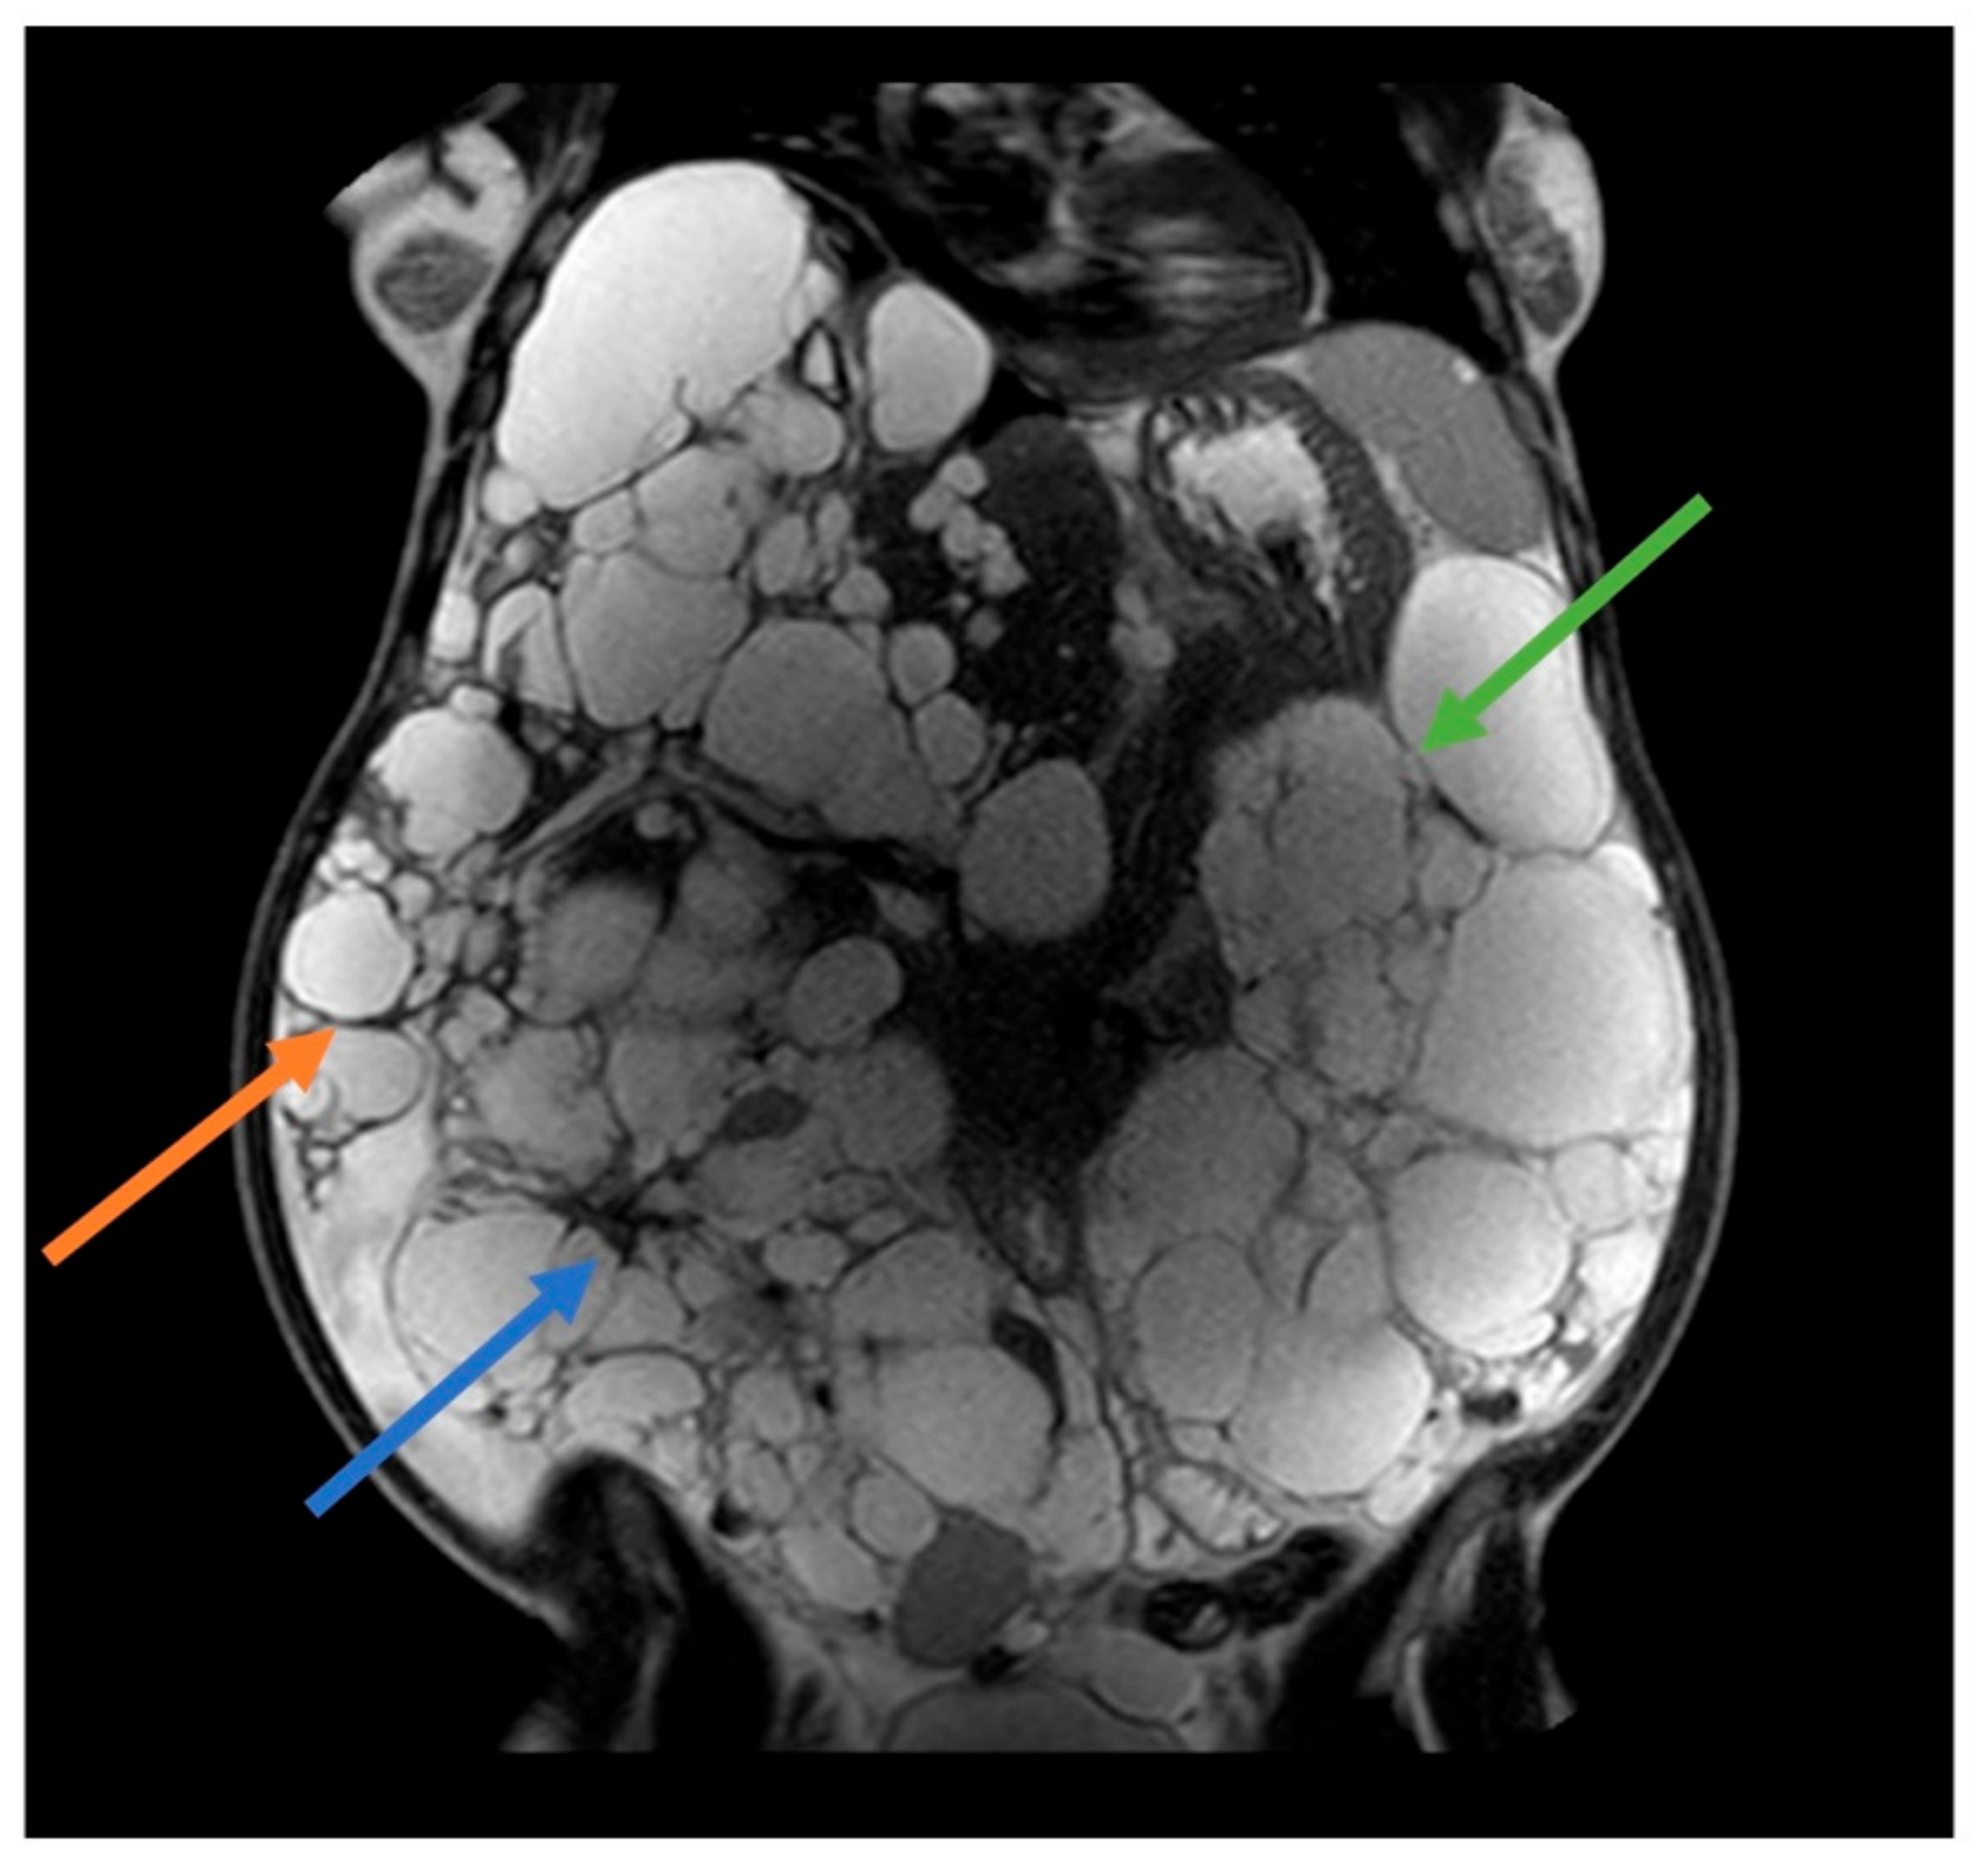

2.1. ADPKD